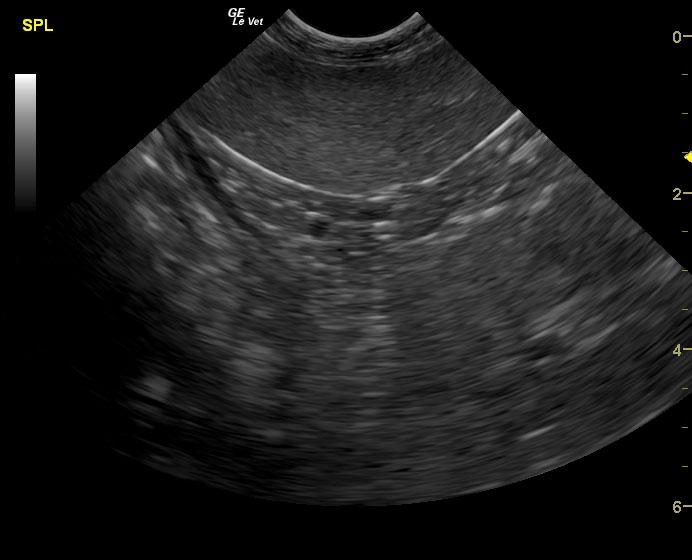

A 14-year-old SF Chow mix was presented for evaluation of weakness, which had also been present a week ago. On physical examination, a palpable abdominal mass was present. Severe non-regenerative anemia and hypoalbuminemia were present on CBC and blood chemistry.